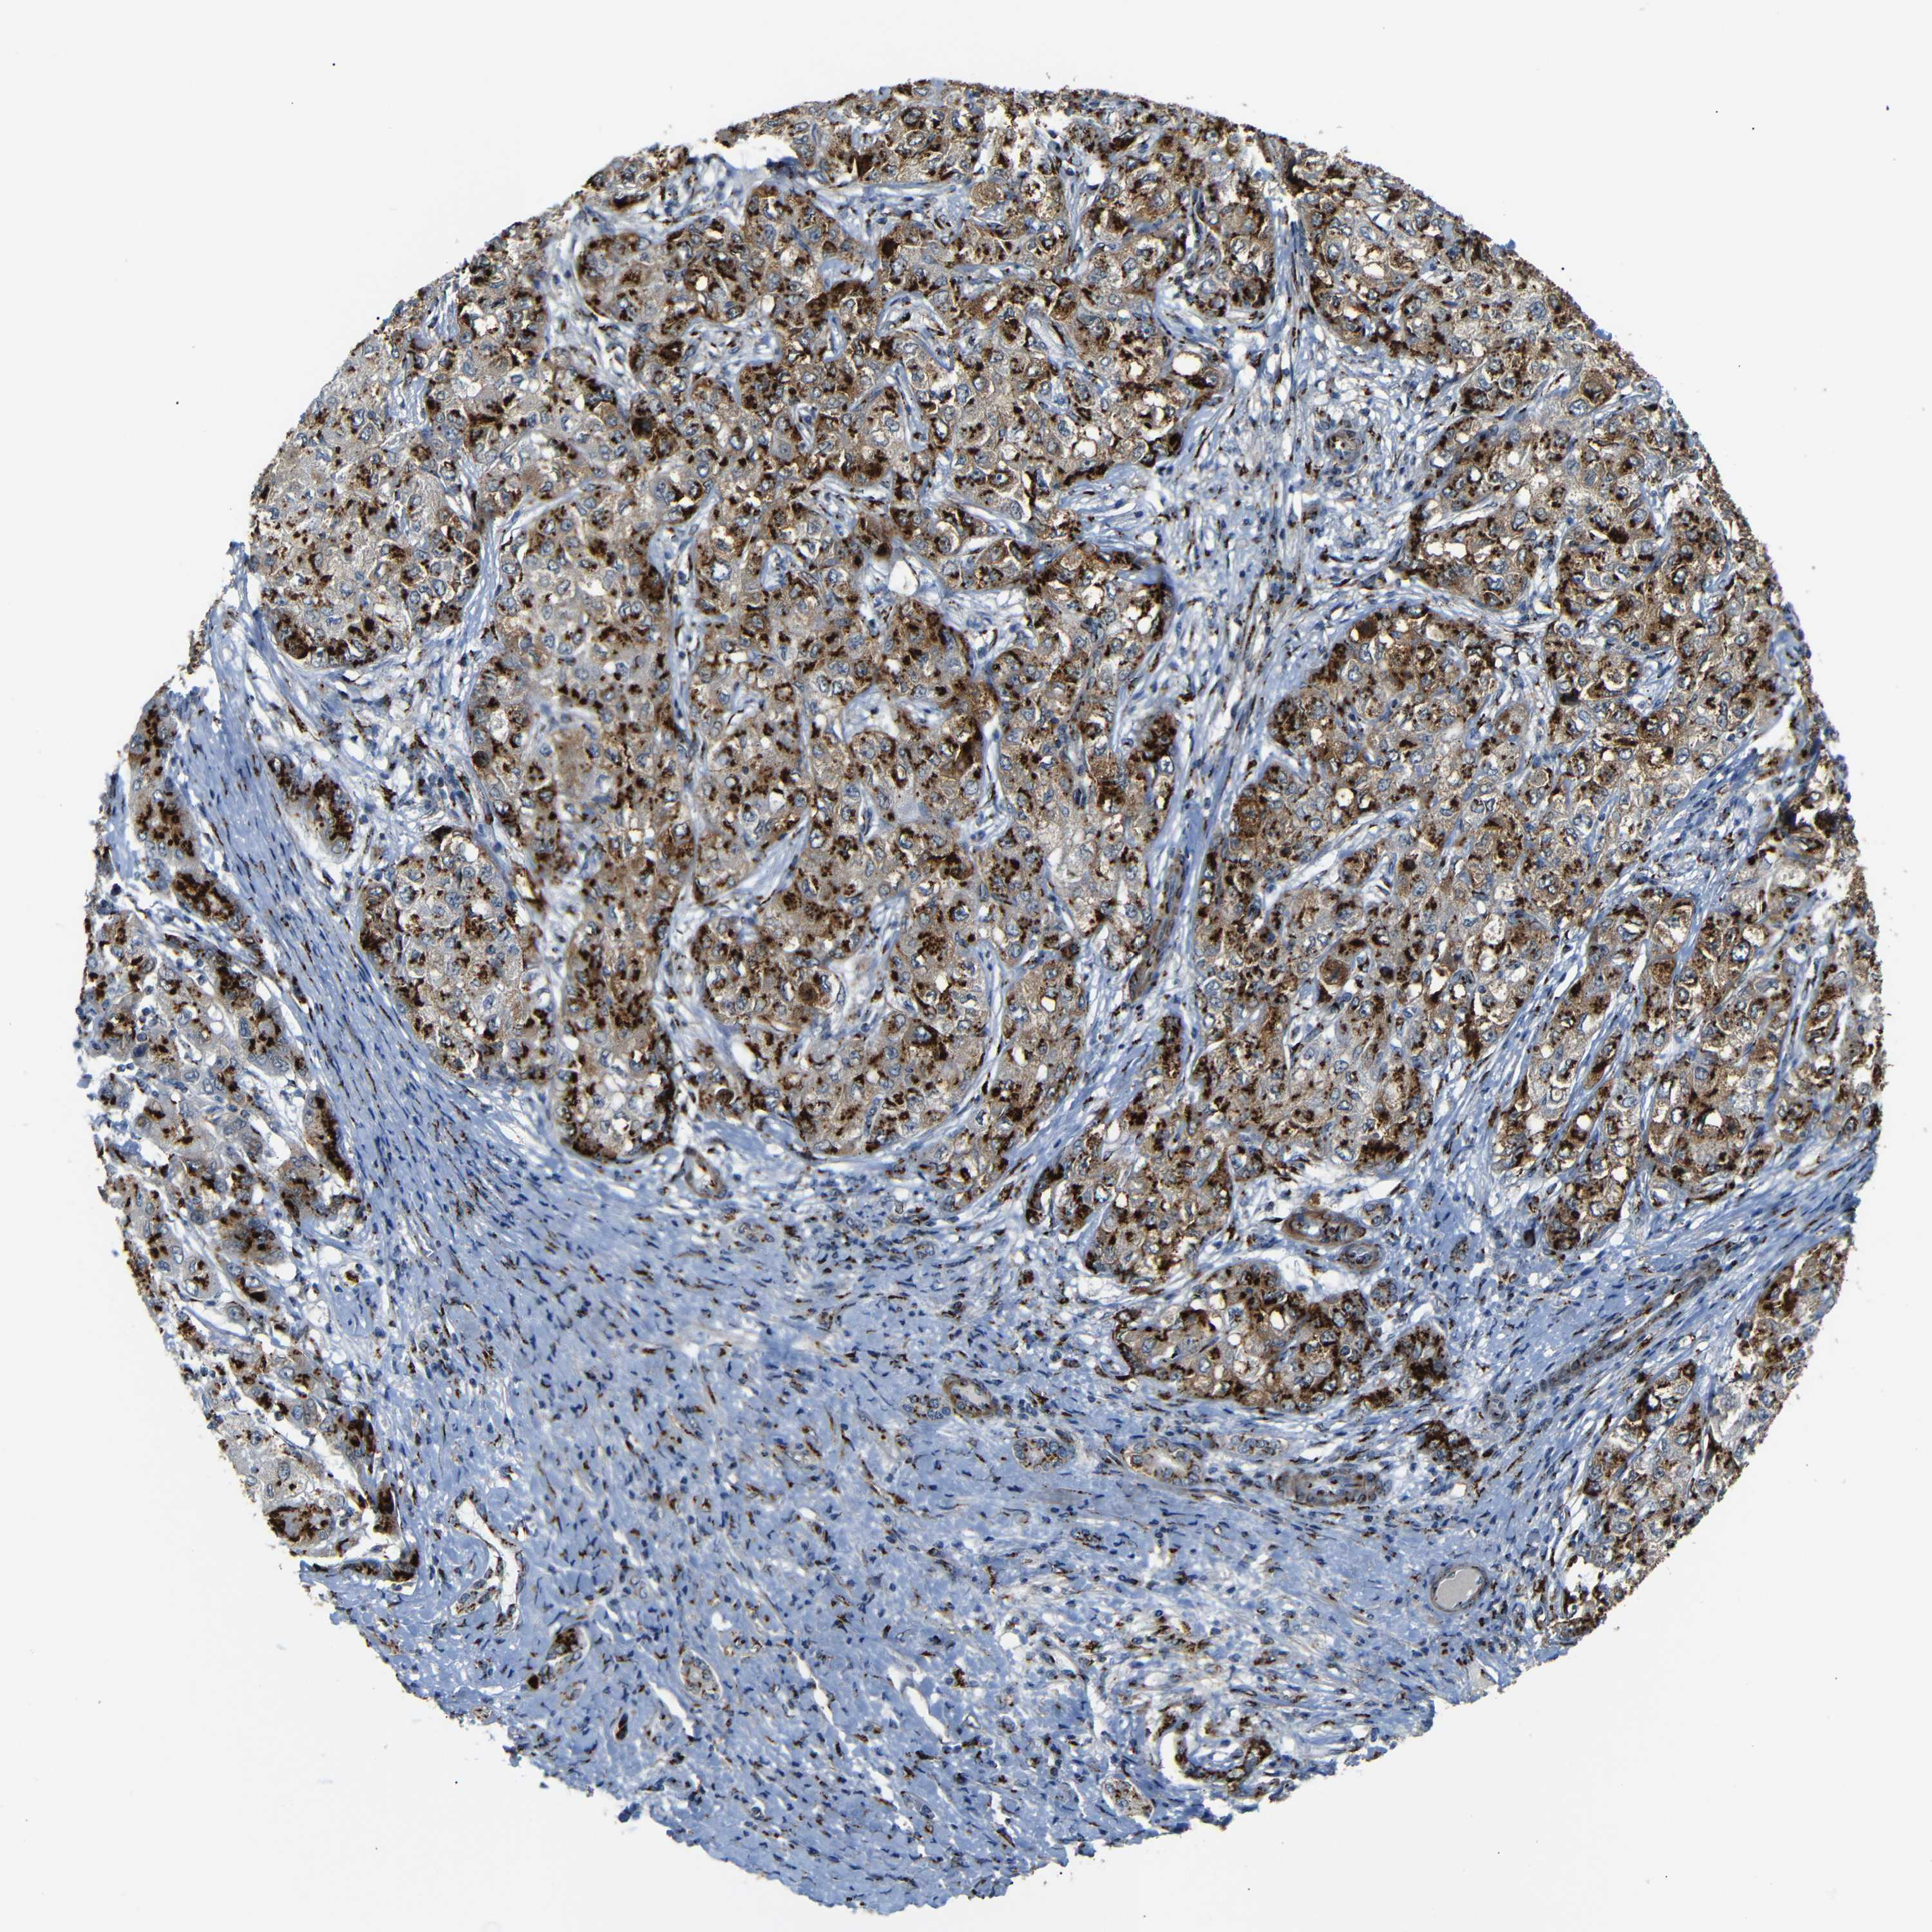

LIVER CANCER - Protein expressioni

A mouse-over function shows sample information and annotation data. Click on an image to view it in a full screen mode. Samples can be filtered based on level of antibody staining by selecting one or several of the following categories: high, medium, low and not detected. The assay and annotation is described here.

Note that samples used for immunohistochemistry by the Human Protein Atlas do not correspond to samples in the TCGA dataset.

Antibody stainingi

Antibody staining in the annotated cell types in the current human tissue is reported as not detected, low, medium, or high, based on conventional immunohistochemistry profiling in selected tissues. This score is based on the combination of the staining intensity and fraction of stained cells.

Each image is clickable and will lead to virtual microscopy that enables deeper exploration of all samples and also displays staining intensity scores, fraction scores and subcellular localization as well as patient and tissue information for each sample.

Antibody HPA012609

Antibody HPA012723

Antibody CAB011489

Staining

High

Medium

Low

Not detected

Intensity

Strong

Moderate

Weak

Negative

Quantity

>75%

75%-25%

<25%

None

Location

Nuclear

Cytoplasmic/membranous

Cytoplasmic/membranous,nuclear

Cholangiocarcinoma

Carcinoma, Hepatocellular, NOS